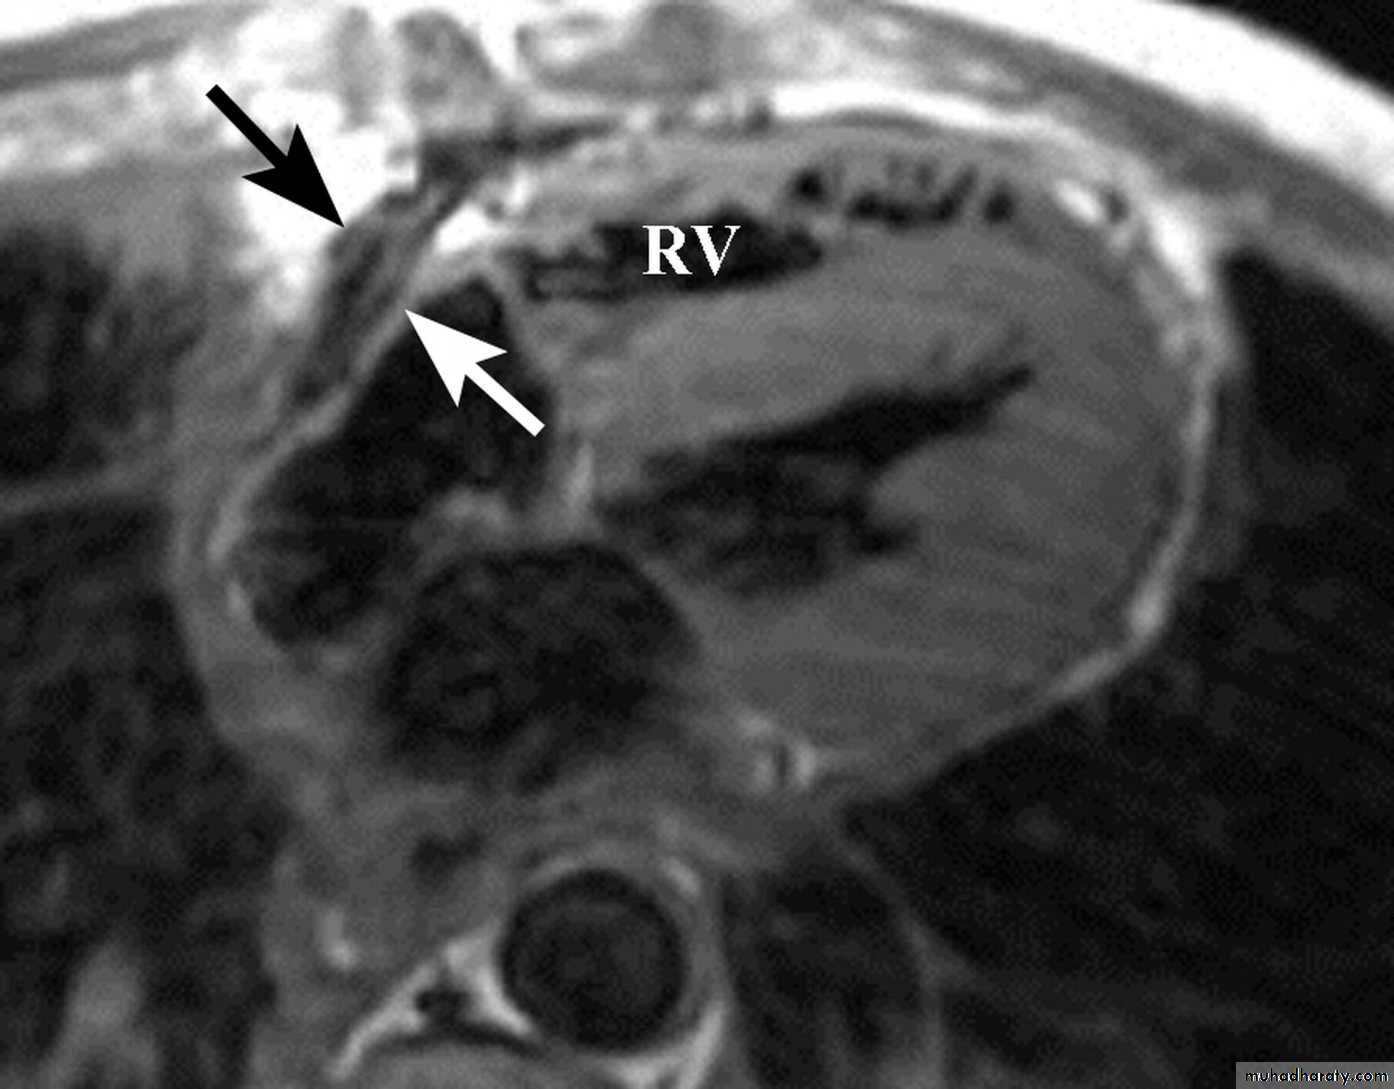

Investigations

Echocardiography & Doppler:RA & LA enlargement

Normal size ventricles

Pericardial thickening

CT/MRI: demonstrate the thickened pericardium